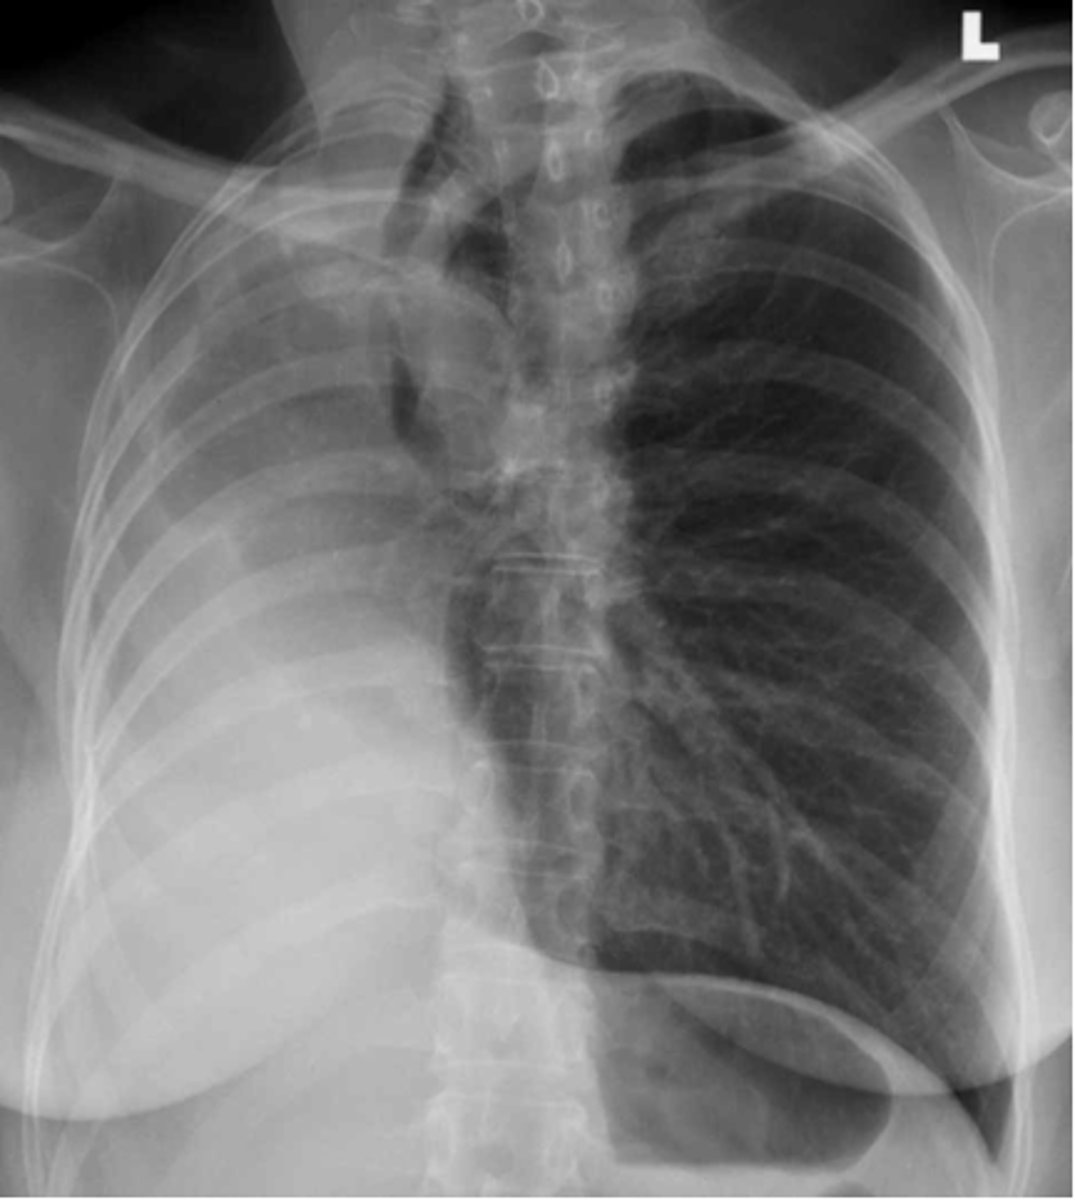

New cards

Pleural effusion

-fluid build up is pushing the mediastinum laterally which causes the t spine to be more visible

-can use lateral decubitus position to confirm presence of effusion/fluid

Dx

<p>Dx</p>